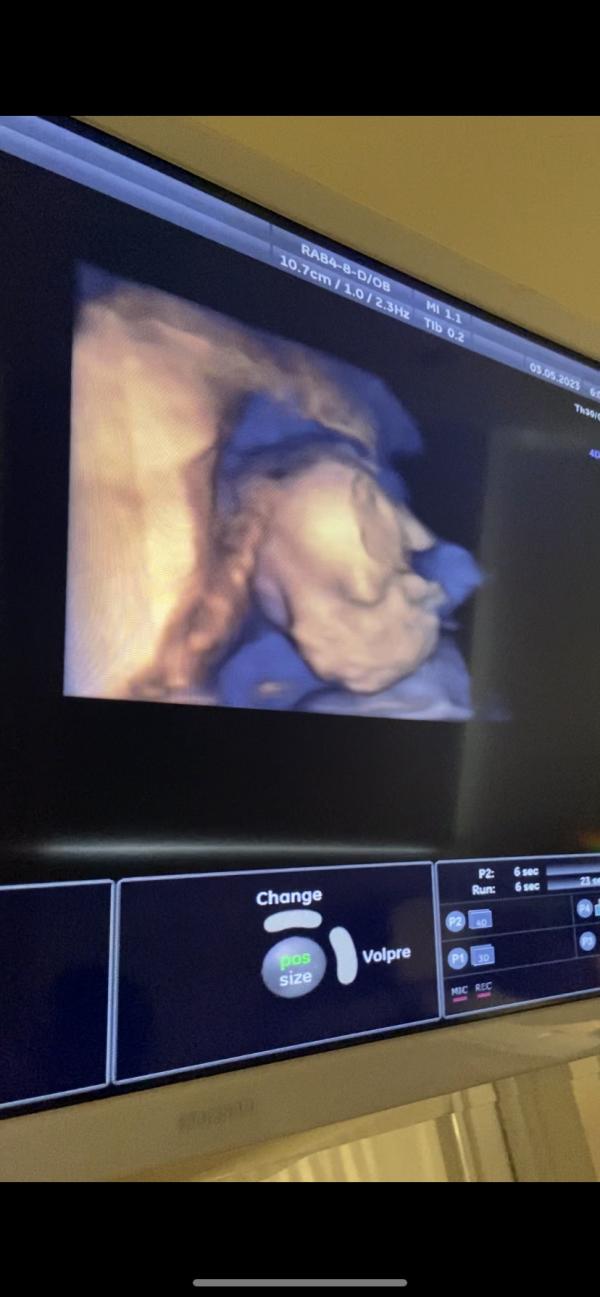

Познакомились с малышом ещё ближе! 3Д УЗИ удивительная вещь😍

Это непередаваемые чувства , когда ты смотришь на своего малыша через экран и находишь сходства с собой👼🏼

Муж сразу сказал, что сыночек похож на меня. Ну на другое я в принципе и не рассчитывала 😁

Ну прям мамин 😍